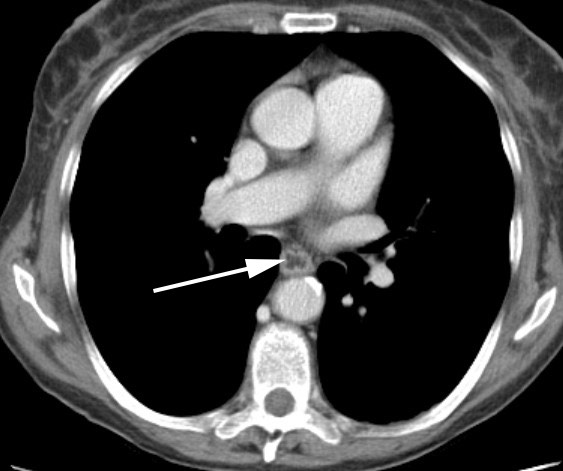

2853. На представленном изображении стрелка указывает на